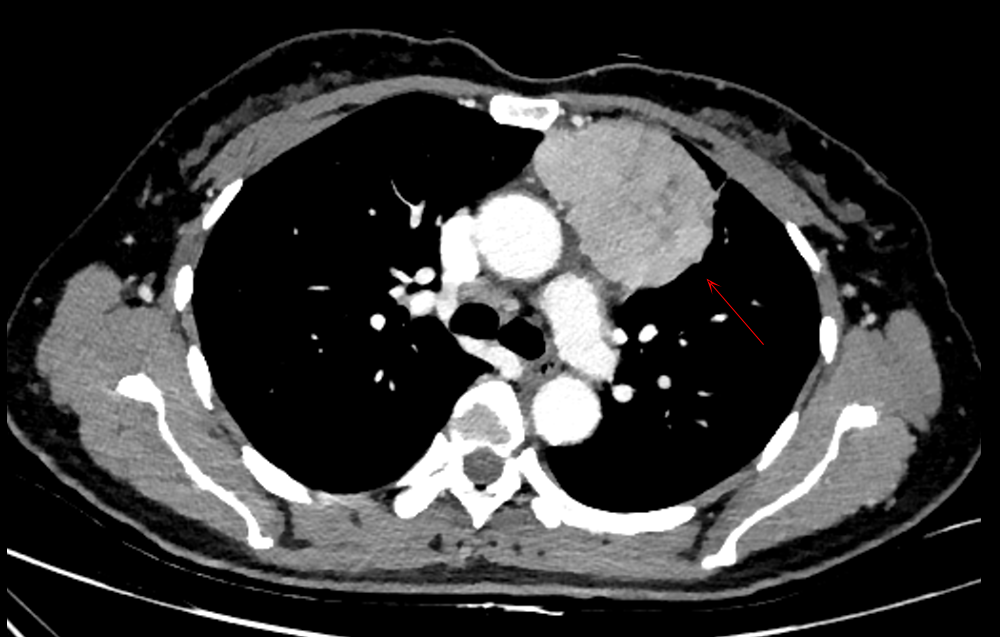

近日,广西壮族自治区南溪山医院胸外科在熊荣生主任医师的带领下,在微创外科领域再获突破,一周内成功完成4例机器人辅助胸腺瘤切除手术。其中,两例尤为典型:一例为直径近 10厘米的巨大胸腺瘤,另一例位于颈胸交界处,均属于胸外科高难度手术。

巨大胸腺瘤:肿瘤体积庞大,紧邻心脏及大血管,稍有不慎即可造成严重并发症;传统胸腔镜在视野和操作灵活性方面受限,往往难以保证安全完整切除,只有正中劈开胸骨,才能做到肿瘤安全、完整切除,但是造成病人的创伤很大。